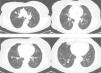

Clinical ObservationThe patient is a 73-year-old woman with no history of interest. Pre-operative chest radiography demonstrated several lung nodules, although the patient was asymptomatic. Hemogram and biochemical determination in serum and urine were normal. Thoracic CT showed multiple bilateral lung nodules of varying sizes between 1 and 10mm, and two larger nodules, one measuring 20mm in the right upper lobe and another measuring 12mm in the right lower lobe (Fig. 1). Lung function tests were normal. Studies searching for a primary neoplastic process, including abdominal/pelvic CT, gynecological assessment and PET/CT, were negative. Endoscopically, the bronchial tree did not present significant alterations, and the cytological and microbiological studies of the bronchoscopic samples (bronchial brushing and suction, and bronchoalveolar lavage) were negative. Fine-needle aspiration of the larger nodule revealed a low-grade fusocellular tumor and neuroendocrine immunophenotype (positive pankeratin, chromogranin and CD56, and negative vimentin and S-100; Fig. 2). Given the multifocal nature of the lesions, we considered the differential diagnosis with metastasis of a mesenchymal neoplasm, melanoma or carcinosarcoma. Video-assisted thoracoscopy provided biopsy samples that showed two carcinoid tumorlets measuring 4 and 3mm in diameter. Immunohistochemistry was positive for CD-56 and TTF-1, and the cell proliferation index (Ki67) was less than 2%. Due to the multiplicity of the process, surgical treatment was ruled out, and chemotherapy was also not considered adequate given the proliferation index. Thus, it was decided to observe the patient. Twenty-four months later, the patient continued to be asymptomatic, with normal lung function, and most of the nodules remained stable, except for minimal growth seen in the two of the largest (3 and 4mm).